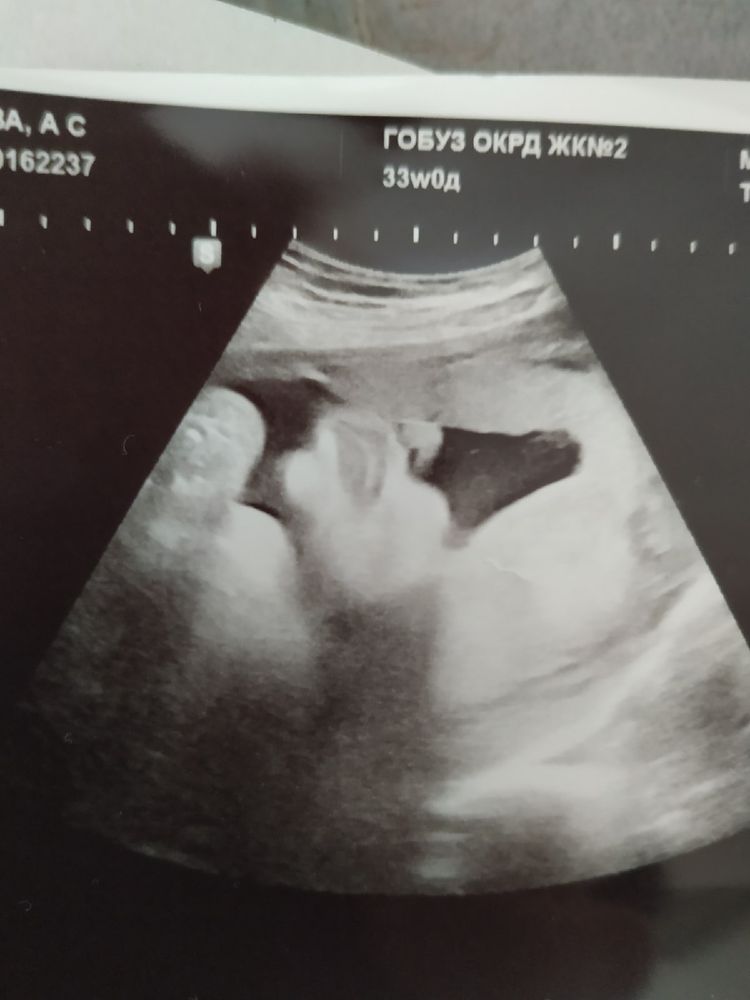

Вот ещё нашла снимочки, дорогие сердцу. Первое фото - это последнее УЗИ, в 33 недели. Вес был 2130.

Зайка моя... Помню, как ты шевелилась на экране, как шевелилась внутри меня, совсем недавно. До сих пор не верится, что все закончилось. Это конец.